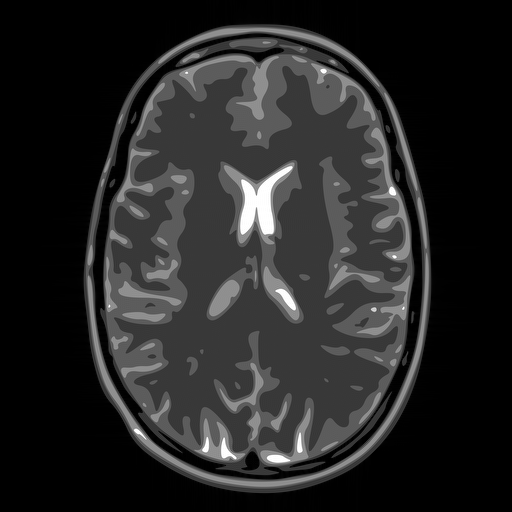

Hence both and should recover equally well. In the top row of Figure 1 we present the result of the flip test for a Gaussian random matrix. As is evident, the reconstructions and are comparable, thus indicating the RIP.

Having considered type II problems, let us now examine the flip test for a type I problem. As discussed, in applications such as MRI, X-ray CT, radio interferometry, etc, the matrix is imposed by the physical sensing device and arises from subsampling the rows of the DFT matrix .111In actual fact, the sensing device takes measurements of the continuous Fourier transform of a function . As discussed in BAACHGSCS ; BAGSAIEP , modelling continuous Fourier measurements as discrete Fourier measurements can lead to inferior reconstructions, and worse, inverse crimes. To avoid this, one must consider an infinite-dimensional compressed sensing approach, as in (2). See AHPRBreaking ; BAGSAIEP for details, as well as PruessmannUnserMRIFast for implementation in MRI. However, for simplicity, we shall continue to work with the finite-dimensional model in the remainder of this paper. Whilst one often has some freedom to choose which rows to sample (corresponding to selecting particular frequencies at which to take measurements), one cannot change the matrix .

It is well known that in order to ensure a good reconstruction, one cannot subsample the DFT uniformly at random (recall that the sparsifying transform is a wavelet basis), but rather one must sample randomly according to an appropriate nonuniform density AHPRBreaking ; Candes_Romberg ; Lustig ; WangAcre . See the bottom left panel of Figure 1 for an example of a typical density. As can be seen in the next panel, by doing so one achieves a great recovery. However, the result of the flip test in the bottom right panel clearly demonstrates that the matrix does not satisfy an RIP. In particular, the ordering of the wavelet coefficients plays a crucial role in the reconstruction quality. To explain this, and in particular, the high-quality reconstruction seen in the unflipped case, one evidently requires a new analytical framework.

Note that the flip test in Figure 1 also highlights another important phenomenon: namely, the effectiveness of the subsampling strategy depends on the sparsity structure of the image. In particular, two images with the same total sparsity (the original and the flipped ) result in wildly different errors when the same sampling pattern is used. Thus we conclude that there is no one optimal sampling strategy for all sparse vectors of wavelet coefficients.